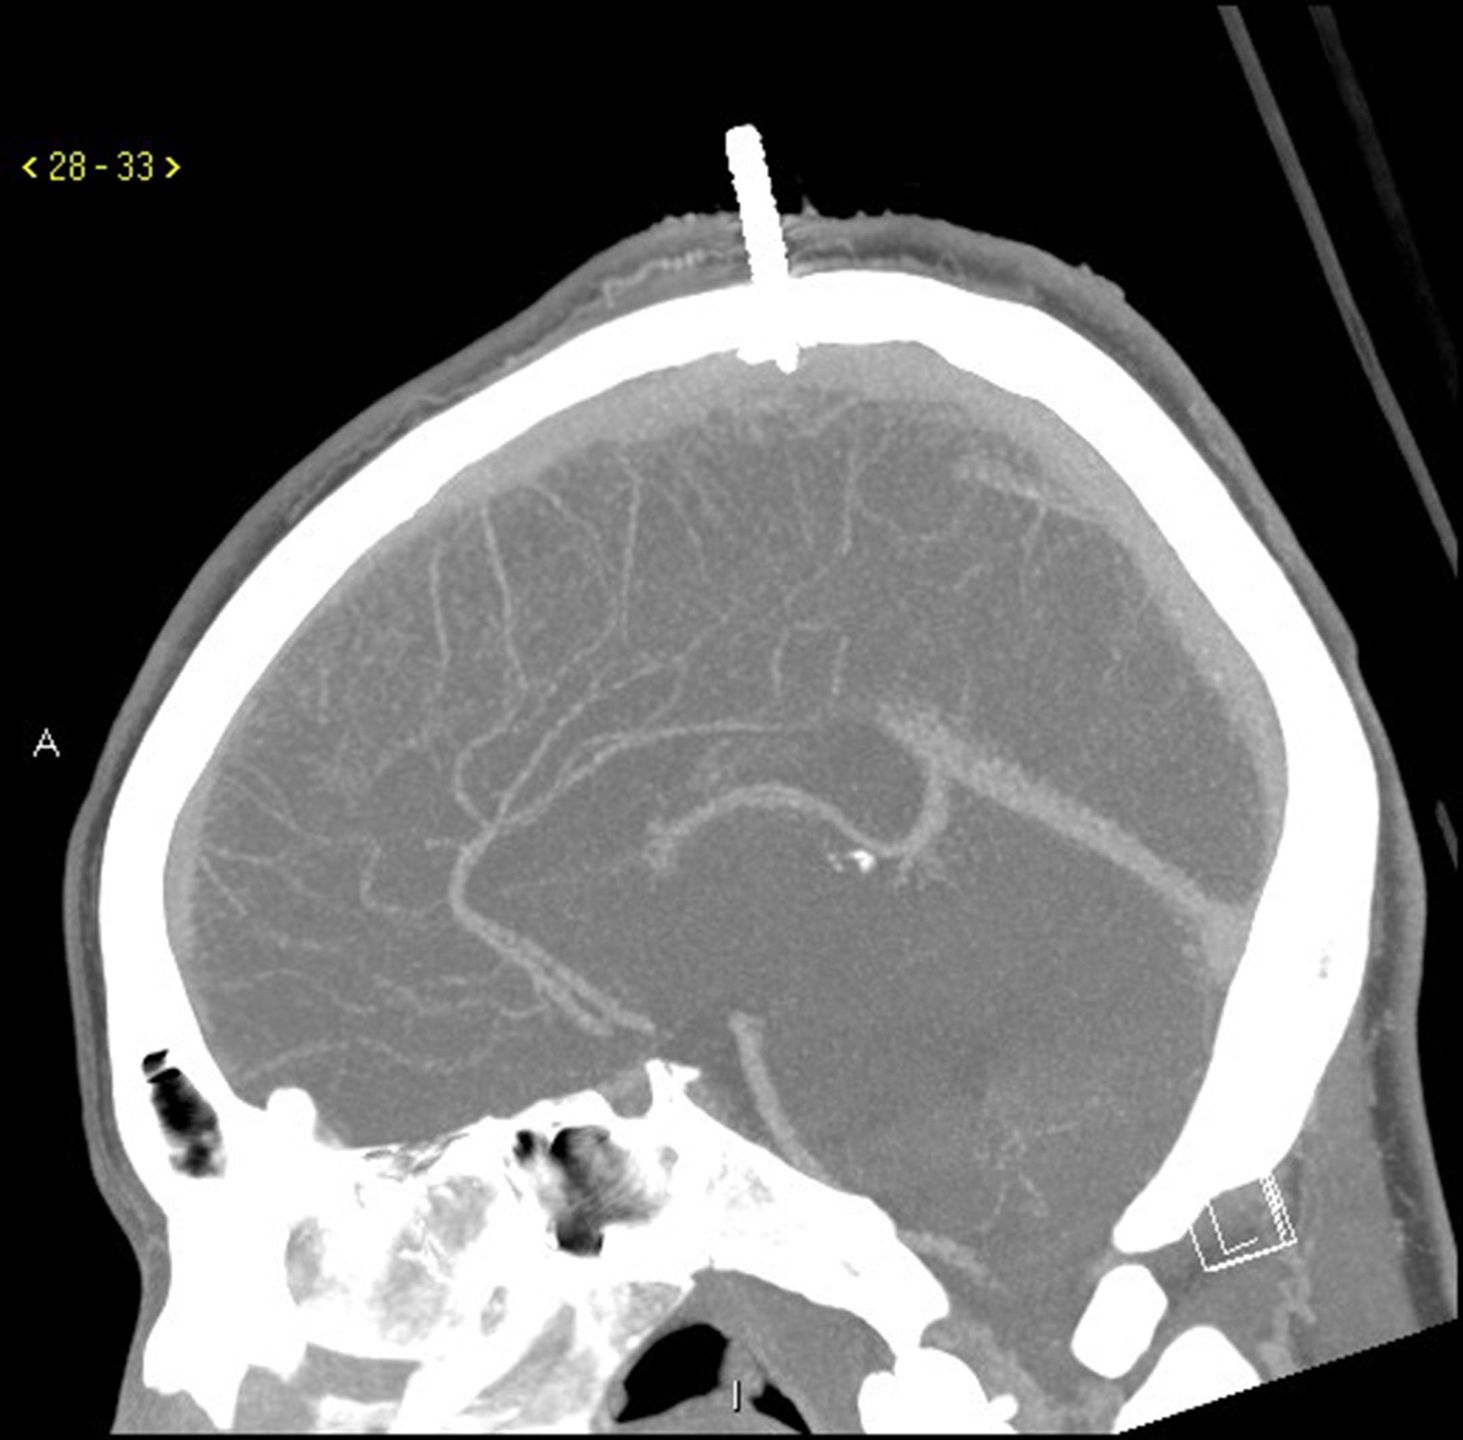

Chłopiec z Maryland w USA przeżył dziwaczny wypadek podczas budowy domku na drzewie. Media w USA opisały właśnie, jak w poprzednią sobotę 13-latka uderzyła w głowę deska, a doczepiony do niej metalowy wkręt przebił mu czaszkę. Darius Foreman konstruował swoją kryjówkę wśród gałęzi drzewa w mieście Salisbury, gdy poślizgnął się i spadł na ziemię, a wraz z nim narzędzia i deski. Jedna z nich nieomal go zabiła. - Myślę, że śmierć była dosłownie o milimetr - stwierdził dr Alan Cohen, szef neurochirurgii na wydziale pediatrii szpitala Johna Hopkinsa w Baltimore.

Dr Cohen dowiedział się od ratujących chłopca strażaków, że deska z gwoździem, która spadła na głowę Dariusa, miała ponad półtora metra długości. Zanim chłopiec trafił do śmigłowca pogotowia udało się ją znacznie skrócić. W ten sposób 13-latek nie wykrwawił się podczas transportu. - On nawet z tą skróconą deską nie był w stanie zmieścić się do pierwszego helikoptera, który przyleciał, więc wezwali drugi, większy - wyjaśnia lekarz.

Chłopca ostatecznie przetransportowano do szpitala Johna Hopkinsa. Operację przeprowadziła żona dr Cohena, która także jest dziecięcym neurochirurgiem. Pierwszym problemem było odczepienie deski od gwoździa. Gdy to się udało zrobić, zmierzono się z czymś dużo trudniejszym, czyli wyciąganiem wkrętu. - Jeżeli byśmy go dosłownie wykręcili, krew byłaby wszędzie - wyjaśnia lekarz.

Chirurdzy zdecydowali się wyciągnąć wkręt, manipulując nim z boku, od środka czaszki. Wywiercili dwa otwory w głowie chłopca, z lewej i prawej strony wkrętu. Dzięki temu uzyskali dostęp do jego czubka. Uniknięto ryzykownego krwawienia, a otwory w głowie dziecka zasłonięto tytanowymi płytkami.